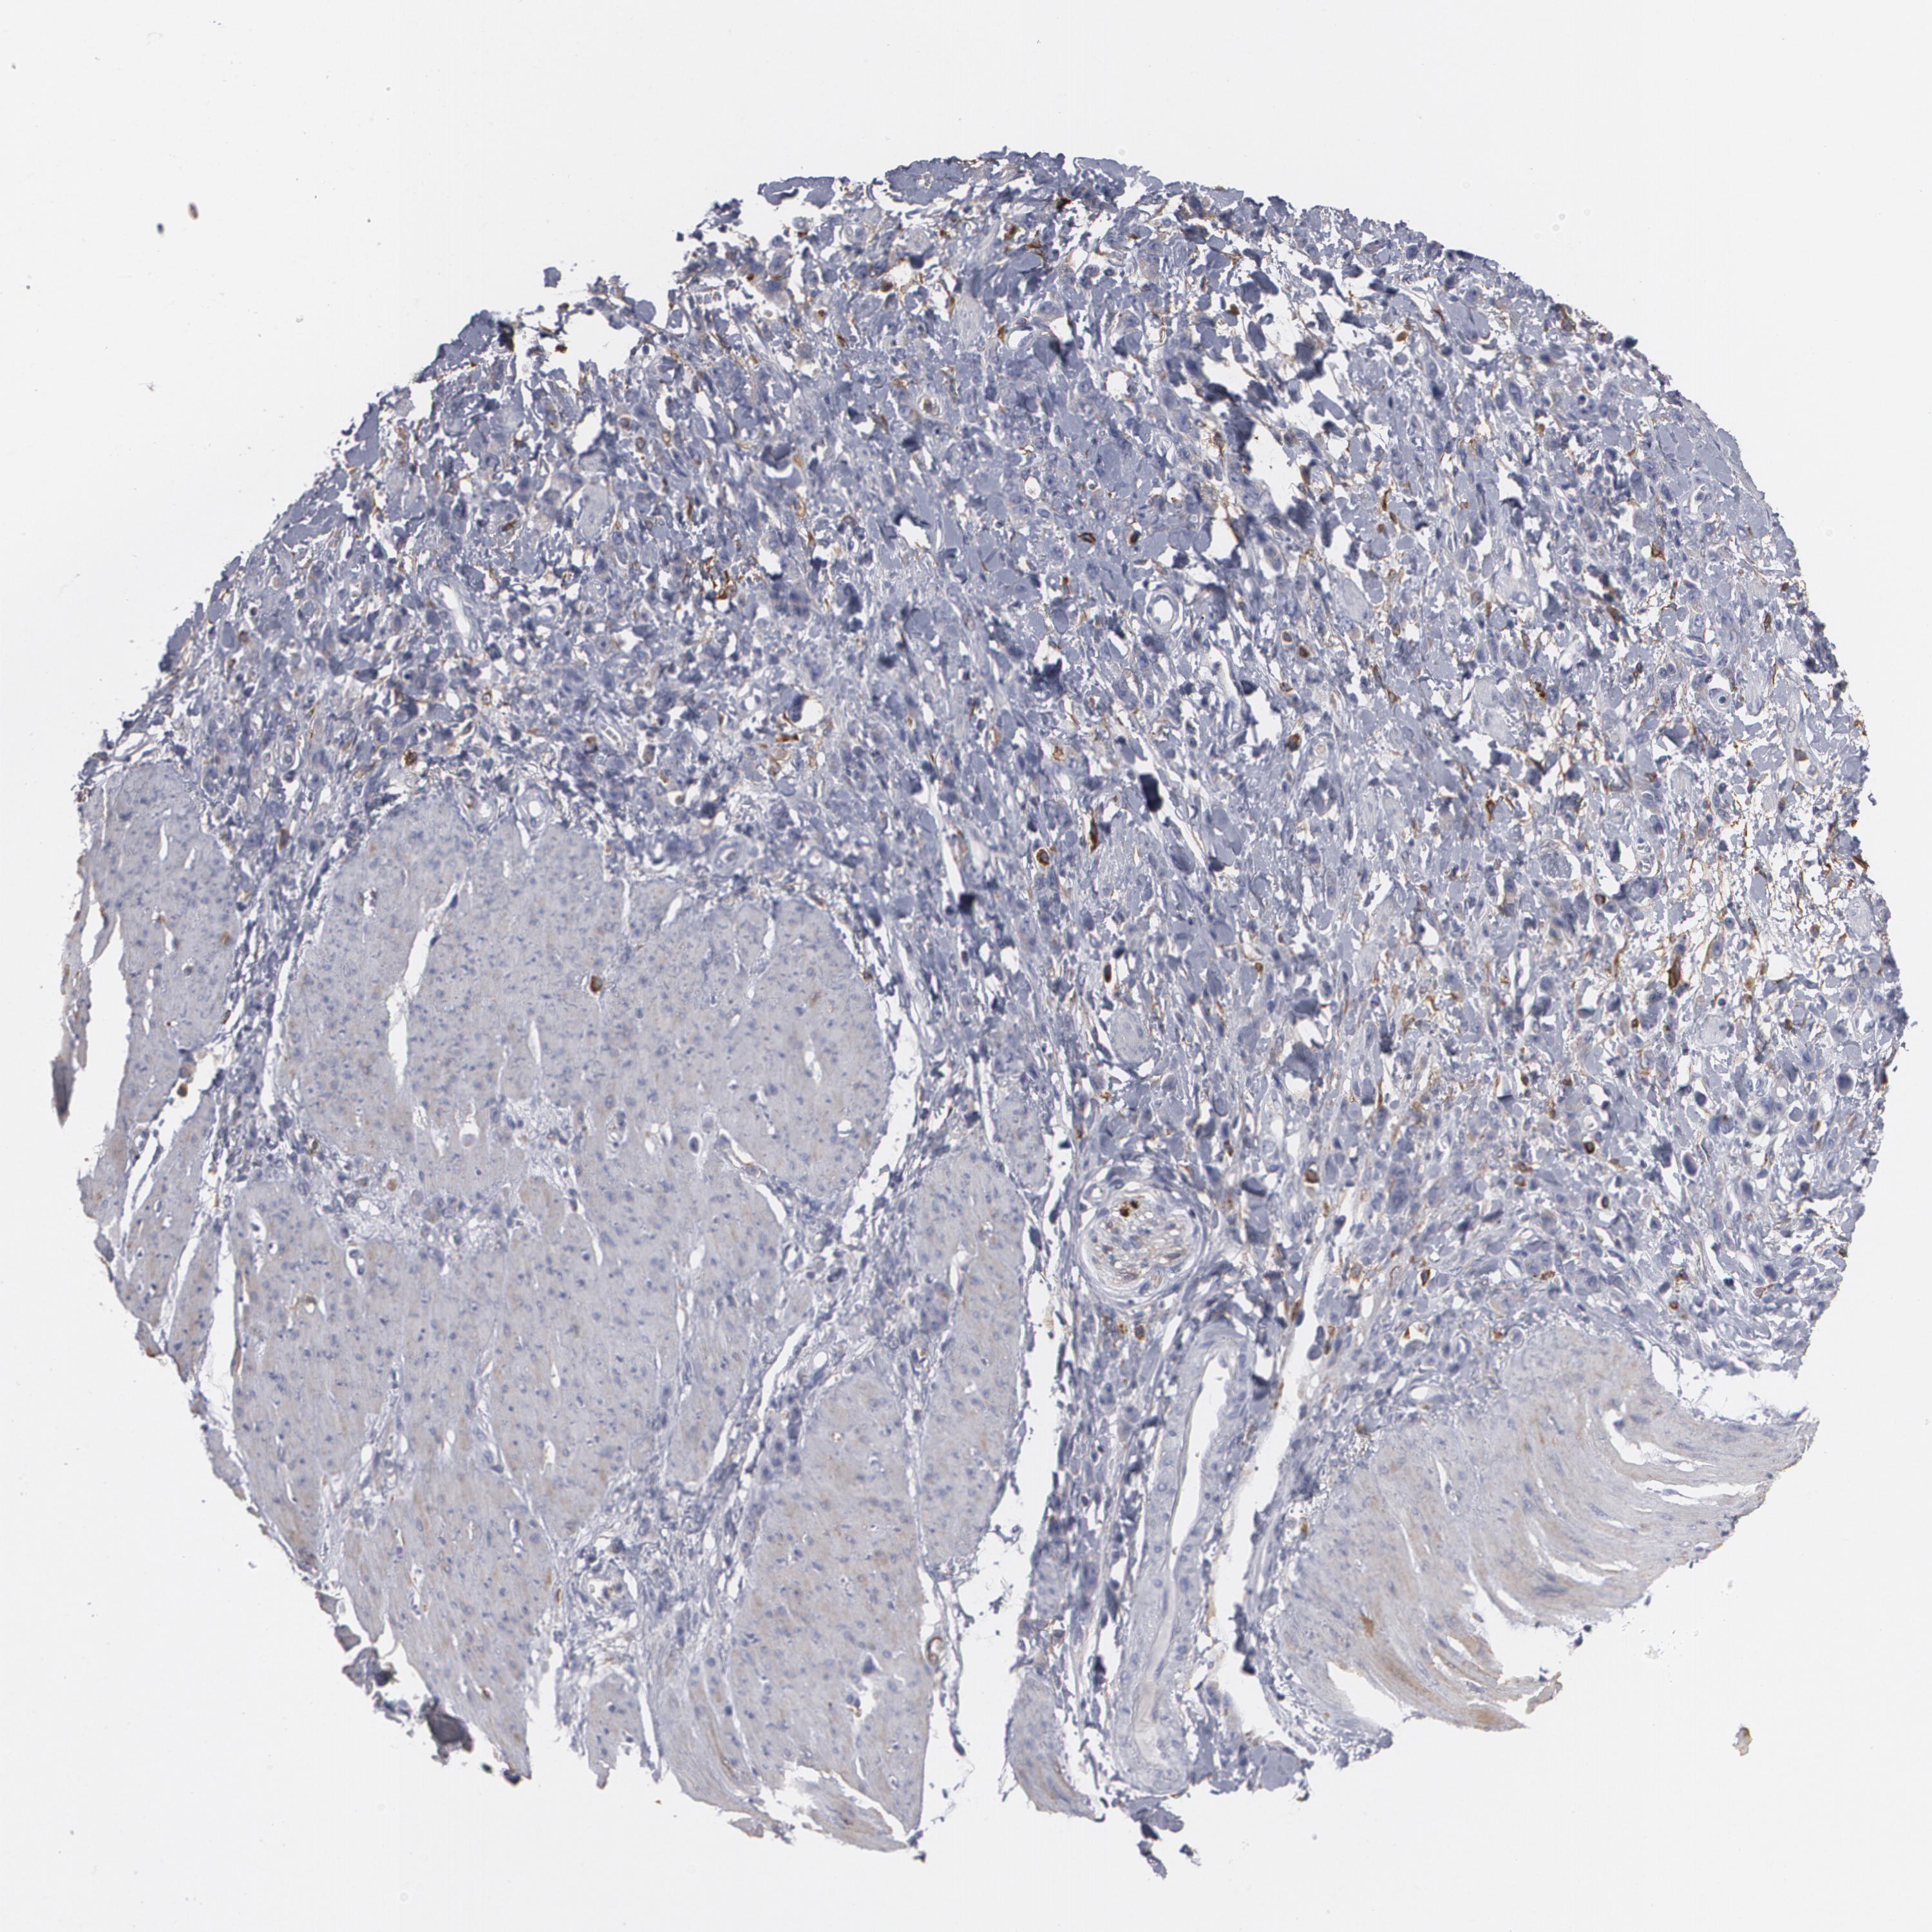

STOMACH CANCER - Protein expressioni

A mouse-over function shows sample information and annotation data. Click on an image to view it in a full screen mode. Samples can be filtered based on level of antibody staining by selecting one or several of the following categories: high, medium, low and not detected. The assay and annotation is described here.

Antibody stainingi

Antibody staining in the annotated cell types in the current human tissue is reported as not detected, low, medium, or high, based on conventional immunohistochemistry profiling in selected tissues. This score is based on the combination of the staining intensity and fraction of stained cells.

Each image is clickable and will lead to virtual microscopy that enables deeper exploration of all samples and also displays staining intensity scores, fraction scores and subcellular localization as well as patient and tissue information for each sample.

Antibody HPA001536

Staining

High

Medium

Low

Not detected

Intensity

Strong

Moderate

Weak

Negative

Quantity

>75%

75%-25%

<25%

None

Location

Nuclear

Cytoplasmic/membranous

Cytoplasmic/membranous,nuclear

Adenocarcinoma, NOS